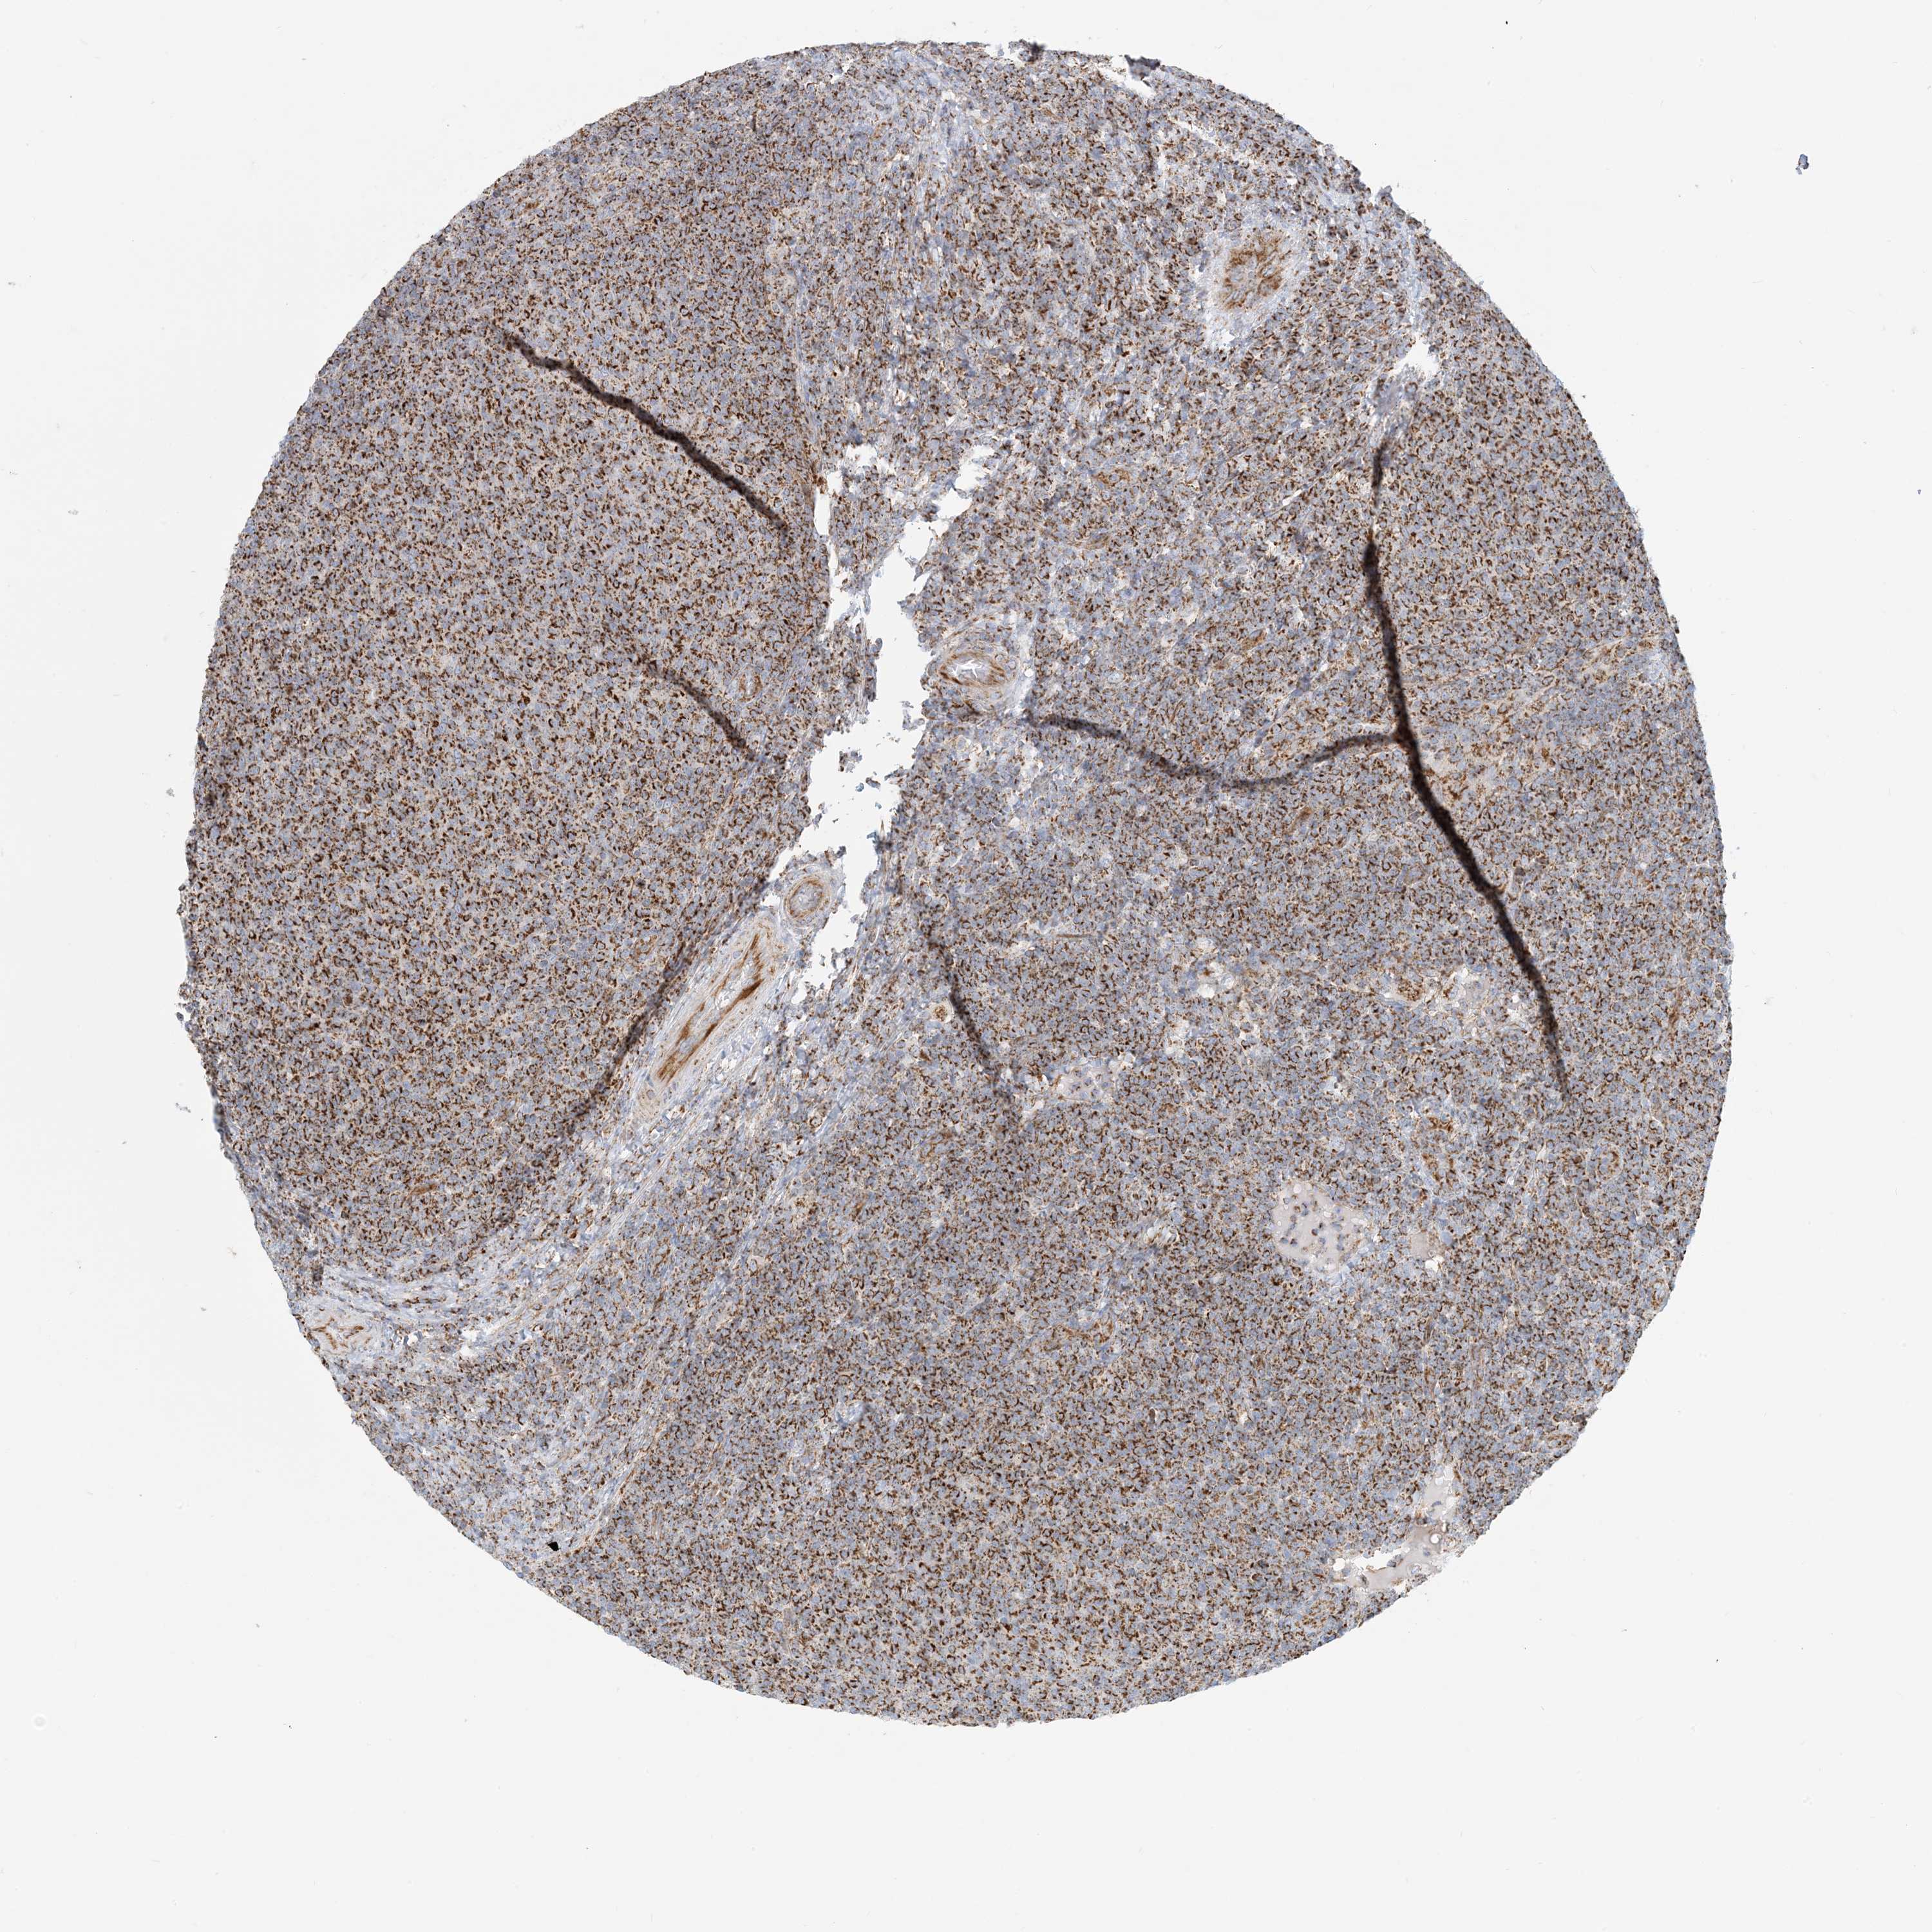

LYMPHOMA - Protein expressioni

A mouse-over function shows sample information and annotation data. Click on an image to view it in a full screen mode. Samples can be filtered based on level of antibody staining by selecting one or several of the following categories: high, medium, low and not detected. The assay and annotation is described here.

Antibody stainingi

Antibody staining in the annotated cell types in the current human tissue is reported as not detected, low, medium, or high, based on conventional immunohistochemistry profiling in selected tissues. This score is based on the combination of the staining intensity and fraction of stained cells.

Each image is clickable and will lead to virtual microscopy that enables deeper exploration of all samples and also displays staining intensity scores, fraction scores and subcellular localization as well as patient and tissue information for each sample.

Antibody HPA031966

Hodgkin's disease, NOS

Malignant lymphoma, non-Hodgkin's type, High grade

Malignant lymphoma, non-Hodgkin's type, Low grade